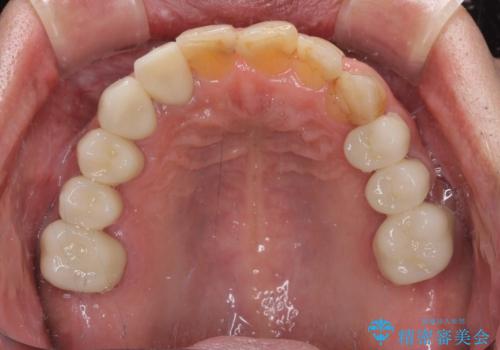

- 前歯のデコボコや、奥歯を咬んだときに痛みがあるとのことで来院された患者様です。

全体的に問題が多く、全てをしっかりと治療したいとのことでした。

全体的に中等度の歯周病と診断されたため、歯周外科処置やインプラントによる咬合回復から進めて行き、矯正治療による歯列改善を行った後にオールセラミッククラウンにて補綴することとしました。

矯正治療を希望して来院されましたが、歯周病を併発していたため、矯正治療開始前の処置が非常に多くなりました。特に歯槽骨の再生治療を行ったため、外科処置後の静置期間が長くなり、4年弱の治療期間となりました。

治療後には咬みやすさだけでなく、前歯が大変審美的に仕上がり、患者様には大変満足していただきました。